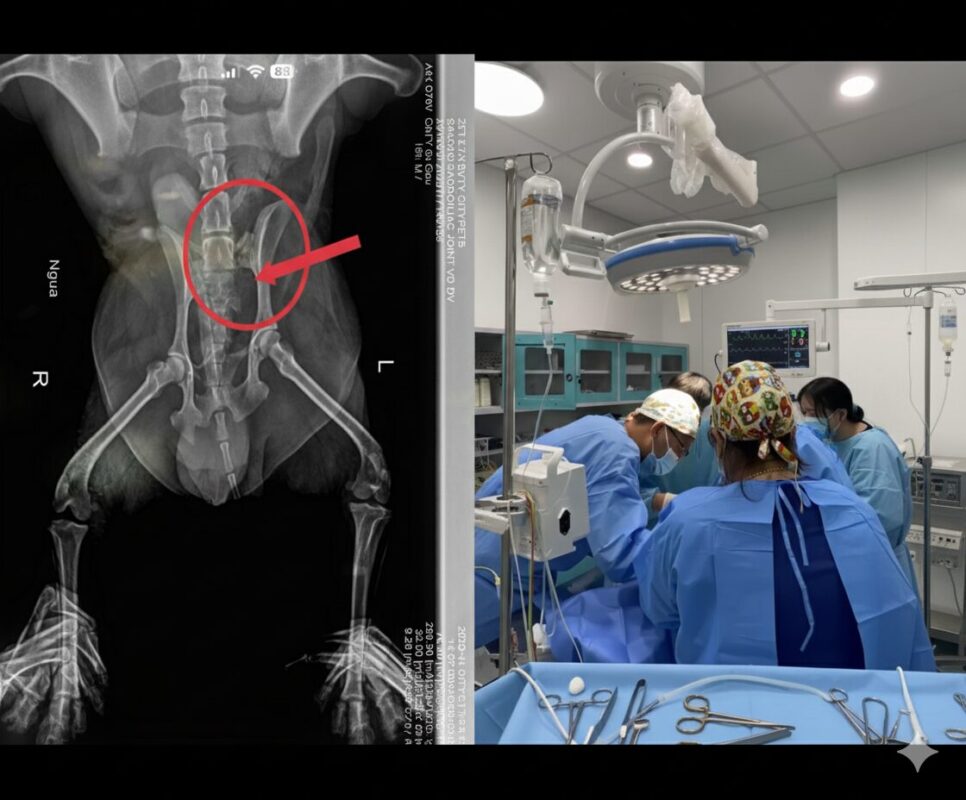

Vừa qua, đội ngũ bác sĩ thú y tại CityPets đã tiếp nhận và tiến hành ca phẫu thuật kéo dài từ 12:00 đêm đến 4:00 sáng cho một bé chó gặp chấn thương nghiêm trọng: gãy xương chậu. Chấn thương này ảnh hưởng trực tiếp đến khả năng vận động, nhưng nhờ sự nhanh chóng trong xử lý và tay nghề chuyên môn cao của đội ngũ bác sĩ, bé đã dần hồi phục sau phẫu thuật.

Hiện tại, bé đang trong quá trình chăm sóc và theo dõi sát sao để đảm bảo sức khỏe và khả năng vận động trở lại bình thường.